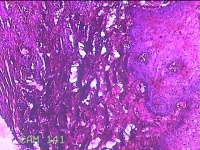

下唇肿物

性别

男

年龄

22岁

临床诊断

口腔黏液腺囊肿

下唇肿物一个月余。

大体所见

图3